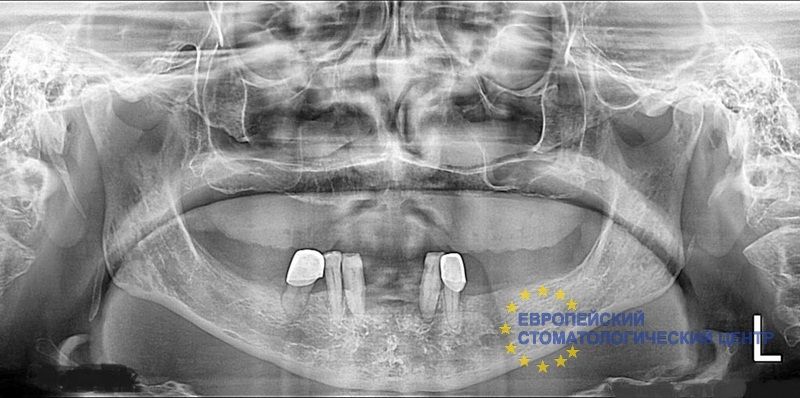

Patient X has atrophy of the alveolar process of the III degree on the upper jaw. He needed alveolar ridge reconstruction and osteoplastic surgery. The installation of basal implants with fixation in the cortical bone was performed. The next day I got teeth.

View before surgery